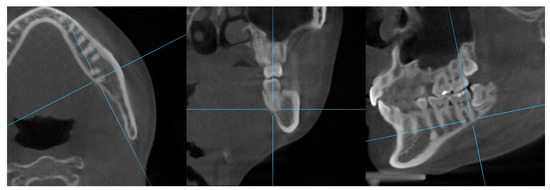

Original CBCT data of the 145 patients (84 men, 61 women, mean age: 22.0 ± 1.76 years) were stored in digital imaging and communications in medicine format and analyzed using Ondemand3D software (Version 1.0, Cybermed, Seoul, Republic of Korea). Two-dimensional lateral and frontal cephalograms were obtained from the reoriented CBCT images (Figure 1).

Figure 1.

Reference planes and landmarks for reorientation of the CBCT images. Nasion, right and left orbitale and right porion were used for reorientation to generate two-dimensional cephalographs. The mandibular occlusal plane was formed by the lower incisor edge (LIE) and right and left mesiobuccal cusps of the mandibular first molars (RMB6, LMB6).

CBCT images were reoriented such that the mandibular occlusal plane passed through the midpoint of the mandibular central incisor edge and right and left mesiobuccal cusps of the mandibular first molar (Figure 1) [2]. The distances between the left and right mandibular molar roots and the inner and outer surfaces of lingual cortical bone were measured (Figure 3).